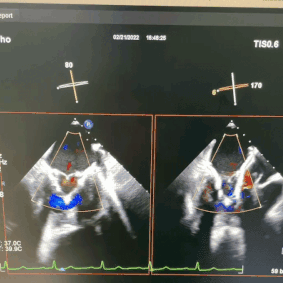

术后超声

基于前期多学科团队的精准评估、术中专业团队精湛高深的手术技巧以及精良的TruDelta®经导管二尖瓣瓣膜系统,本次手术圆满成功,术后即刻超声显示二尖瓣反流消失,瓣膜植入位置理想,支架贴合牢固,无瓣周漏,二尖瓣前向血流通畅,结果令人满意。